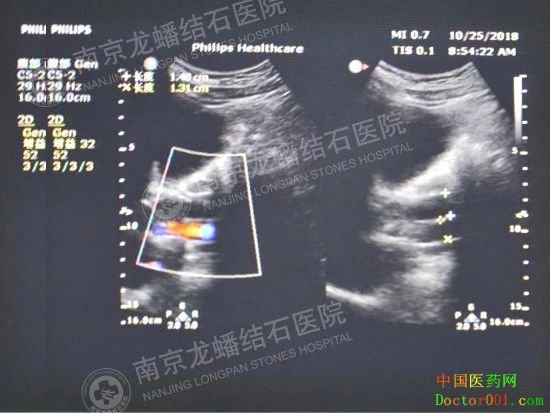

根据陆先生的初步检查情况,医生猜测:可能是胆结石继发胆囊炎,炎症刺激导致胆总管阻塞,进而引发黄疸出现。另外也可能是有结石掉入胆总管,引发阻塞,出现黄疸。这种情况还是比较严重的,可能会导致许多并发症出现,所以建议陆先生尽早去专业的结石医院进一步检查及治疗。 通过网上查询,陆先生了解到南京龙蟠结石医院是一家结石专科医院,不仅患者的满意度很高,且是南京仅有的一家省级结石专科医院,10月25日,陆先生在家人的陪伴下立即前来求诊。 入院后经过全面的身体检查,确诊“胆囊结石伴急性胆囊炎、胆总管结石、乙型肝炎”。

“手有金刚钻,敢揽瓷器活”,蒋清华院长凭着多年来微创取石的丰富手术经验,选用精良的手术设备,凭着过硬的内镜技术,于10月30日上午8点55分,携同肝胆外科专家团队为陆先生施行腹腔镜胆囊切除+胆总管探查取石术,用进口取石网篮从胆总管取出3枚暗褐色结石,大小约1.5*1.0*0.8cm,胆道镜探查胆总管无结石残留后结束手术。 术后40多天后,陆先生返院复查,身体恢复很好,十分感谢我院蒋清华院长及龙蟠肝胆外科专家团队,特地送来一面印有“医德人格同样生辉,医术爱心完美结合”的锦旗,以表诚挚谢意。蒋院长说“愿人间永远有天使,这是对我这身白大褂最高的赞誉!”